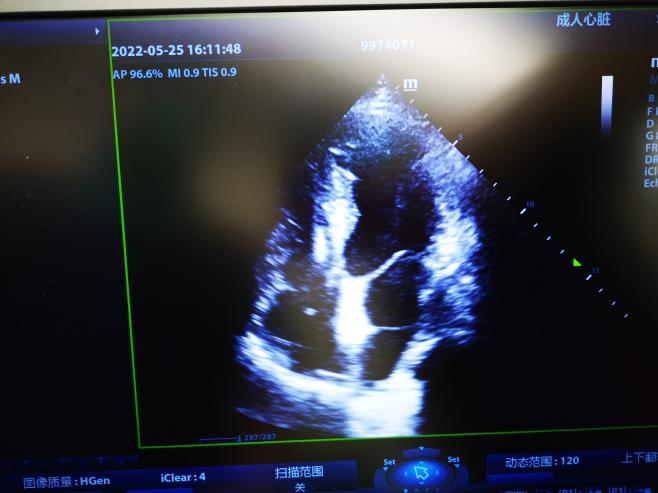

手术在局麻下进行,右股静脉穿刺后,行右心导管检查评估肺高压、肺毛细血管楔压和右房压,计算肺阻力和心排量,然后再经胸超声引导下穿刺房间隔,测量左房压力、左向右压差符合左心衰血流动力学障碍特点,不合并毛细血管前性肺高压。确定合适规格的心房分流器,选择8mm高压球囊扩张后,送入6mm分流器释放于房间隔两侧。推拉试验分流器固定稳定、位置良好,透视下孔径符合预期目标,测量左房压、肺动脉压均较植入前下降,右房压无升高,左向右分流为少量,床旁超声可见分流器夹持于房间隔两侧,分流流速1.4m/s。评估达到预期效果,释放分流器。术后12h患者下床活动,无任何胸闷、头晕不适,活动量较术前改善,六分钟步行距离446米。目前患者已顺利出院,期待后续随访情况。

图2术后超声评价